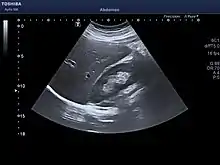

Adult ultrasound showing the right lobe of the liver and right kidney

At birth, the liver comprises roughly 4% of body weight and weighs on average about 120 g (4 oz). Over the course of further development, it will increase to 1.4–1.6 kg (3.1–3.5 lb) but will only take up 2.5–3.5% of body weight.[38]